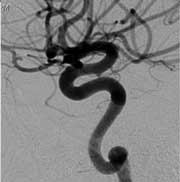

An aneurysm six months after treatment with the Pipeline technology

A self-expanding blood flow diverter that is placed across the neck of an intracranial aneurysm, the Pipeline device maintains blood flow through the parent vessel while disrupting flow within the aneurysm sac itself, leading to stagnation and eventual thrombosis formation. The technology provides a scaffold for endothelial growth, leading to the formation of a biological seal and exclusion of the aneurysm from the circulation.

A braided, cobalt chromium and platinum stent-like device, it is loaded into and delivered via a microcatheter and is currently manufactured in lengths of 10-35mm with diameters in 0.25mm increments from 2.5-5mm. Multiple devices can be used within each other or in sequence to increase the overall length of the construct or to increase the metal surface coverage within an aneurysm.